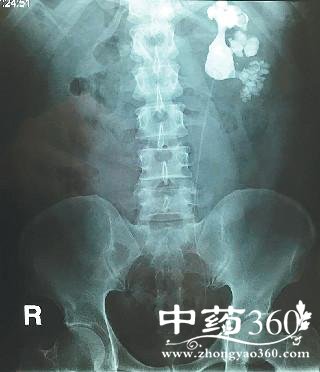

陈先生的儿子陈帅(化名)住在城里,知道父亲有这个毛病,前段时间,他带父亲去新桥医院做B超检查,片子上显示他右肾内长满了结石,形状像鹿角一样。当时,陈先生不敢相信,对检查结果持有怀疑态度。最终,陈先生在儿子的劝导下做了手术,医生通过腹腔镜在陈先生的肾盂上开刀,取出了143块结石。